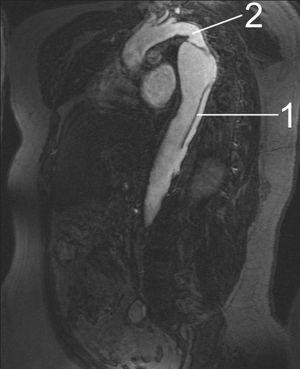

자기 공명 영상(MRI)은 대동맥 박리의 탐지 및 평가에도 사용되며, 민감도는 98%, 특이도는 98%이다. 대동맥 MRI 검사는 대동맥의 3차원 재구성을 생성하여 의사가 내막 파열의 위치와 분지 혈관의 침범을 결정하고 2차 파열을 찾을 수 있도록 한다. 이는 비침습적 검사이며, 요오드화 조영제를 사용할 필요가 없고, 대동맥 부전의 정도를 감지하고 정량화할 수 있다.

대동맥 박리의 경우 MRI 검사의 단점은 더 큰 병원에서만 사용할 수 있고, 검사 시간이 비교적 오래 걸려 이미 상태가 매우 좋지 않은 사람들에게는 위험할 수 있다는 것이다. MRI 촬영 시 사용되는 고강도 자기장으로 인해 금속 임플란트가 있는 개인에게는 사용할 수 없다. 또한, 일부 개인은 MRI 자석에 둘러싸이면 폐소 공포증을 경험한다.

격심한 통증으로부터 대동맥 박리를 의심한다. 흉부 X선으로 대동맥 음영이나 상부 종격동의 확대를 볼 수 있지만, 특히 소견이 보이지 않는 경우도 있기 때문에 기본적으로 CT이나 MRI로 진단한다.

; MRI

: 다양한 단면에서 선명한 영상을 얻을 수 있는 것이 특징이다. 박리의 범위와 상태를 정확하게 파악하는 데 적합하다. 민감도·특이도는 모두 96%.